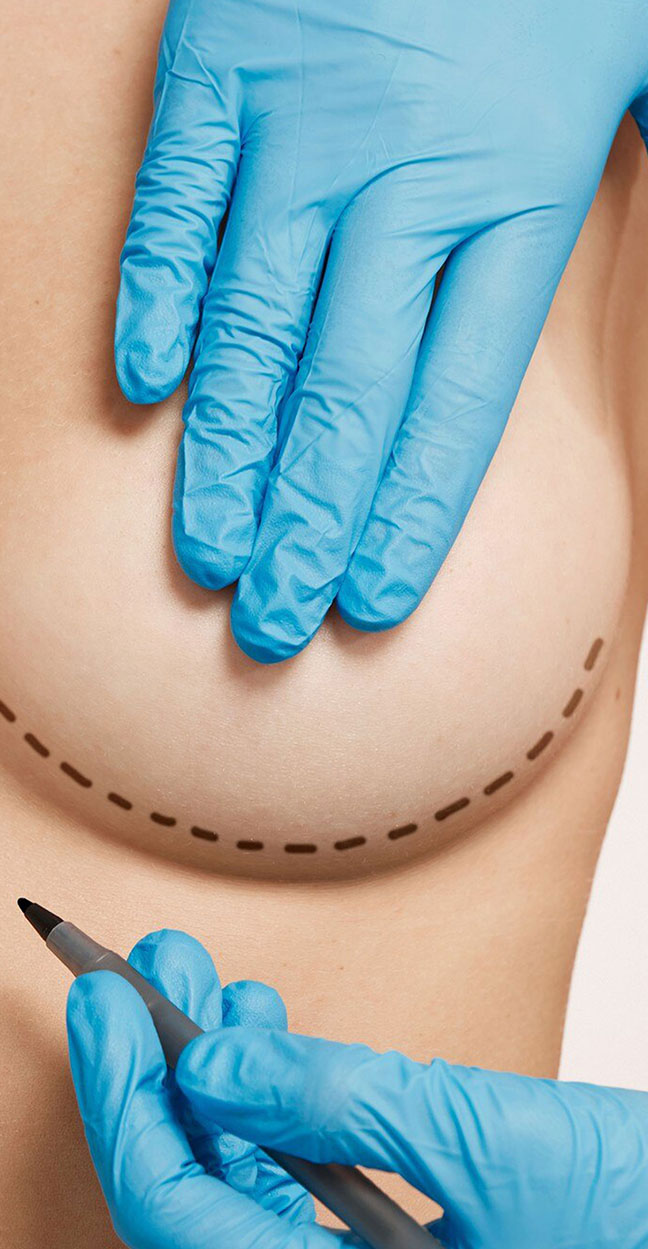

services

We understand that navigating the healthcare system can be overwhelming. That’s why we offer a comprehensive range of services to guide you at every step, making your healthcare journey simpler and more manageable.

At Nydra, We help connect you with carefully selected clinical partners.

Our clinical partners are carefully selected for their experience, qualifications, and commitment to excellence. What sets us apart is our team of healthcare professionals who work in your home country—ensuring that you have the support and guidance needed to make informed decisions, and that quality is always guaranteed.

Our team includes healthcare professionals who carefully assess and coordinate each case, ensuring patients are matched with the most suitable clinical partners.

clinical partners